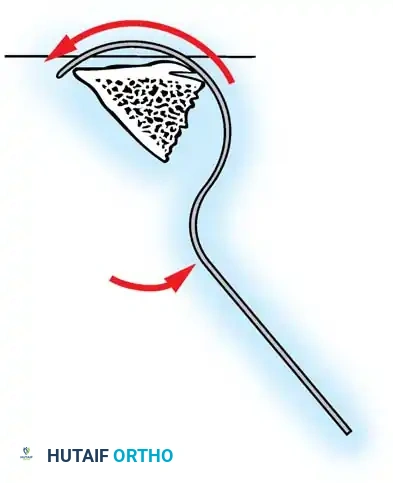

The Moe Technique (Thoracic Spine)

The Moe technique is a highly effective method for achieving intra-articular arthrodesis in the coronally oriented thoracic facet joints.

Fig. 38-26: The Moe technique of thoracic facet fusion, demonstrating the creation of hinged bone flaps.

- Expose the spine fully to the tips of the transverse processes.

- Using a sharp osteotome or Cobb gouge, begin a cut over the cephalad articular process at the base of the lamina.

- Carry this cut along the transverse process almost to its tip. Bend this cortical fragment laterally so it lies between the transverse processes, ideally leaving it hinged on its lateral periosteal attachment to preserve local vascularity.

- Thoroughly denude all articular cartilage from the superior articular process using a sharp curet.

- Make a secondary cut in the superior articular facet, working medially to laterally, producing another hinged fragment.

- Pack the resulting intra-articular defect tightly with cancellous bone graft.